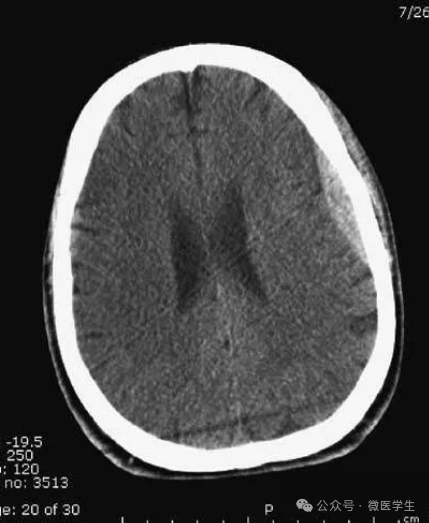

高血压性脑出血:

- 自发性出血;

- 继发于长期高血压及慢性血管病;

- 常见于基底节区、丘脑、脑桥、小脑。

A:占位效应,相邻脑沟、脑池消失;

F:脑出血破入四脑室。

▲

钩回疝:

是当代偿机制不能适应占位性病变时的结果。

基底节区大量高血压性脑出血,破入脑室及蛛网膜下腔,周围水肿,脑干周围空间消失;脑干出血、脑积水。